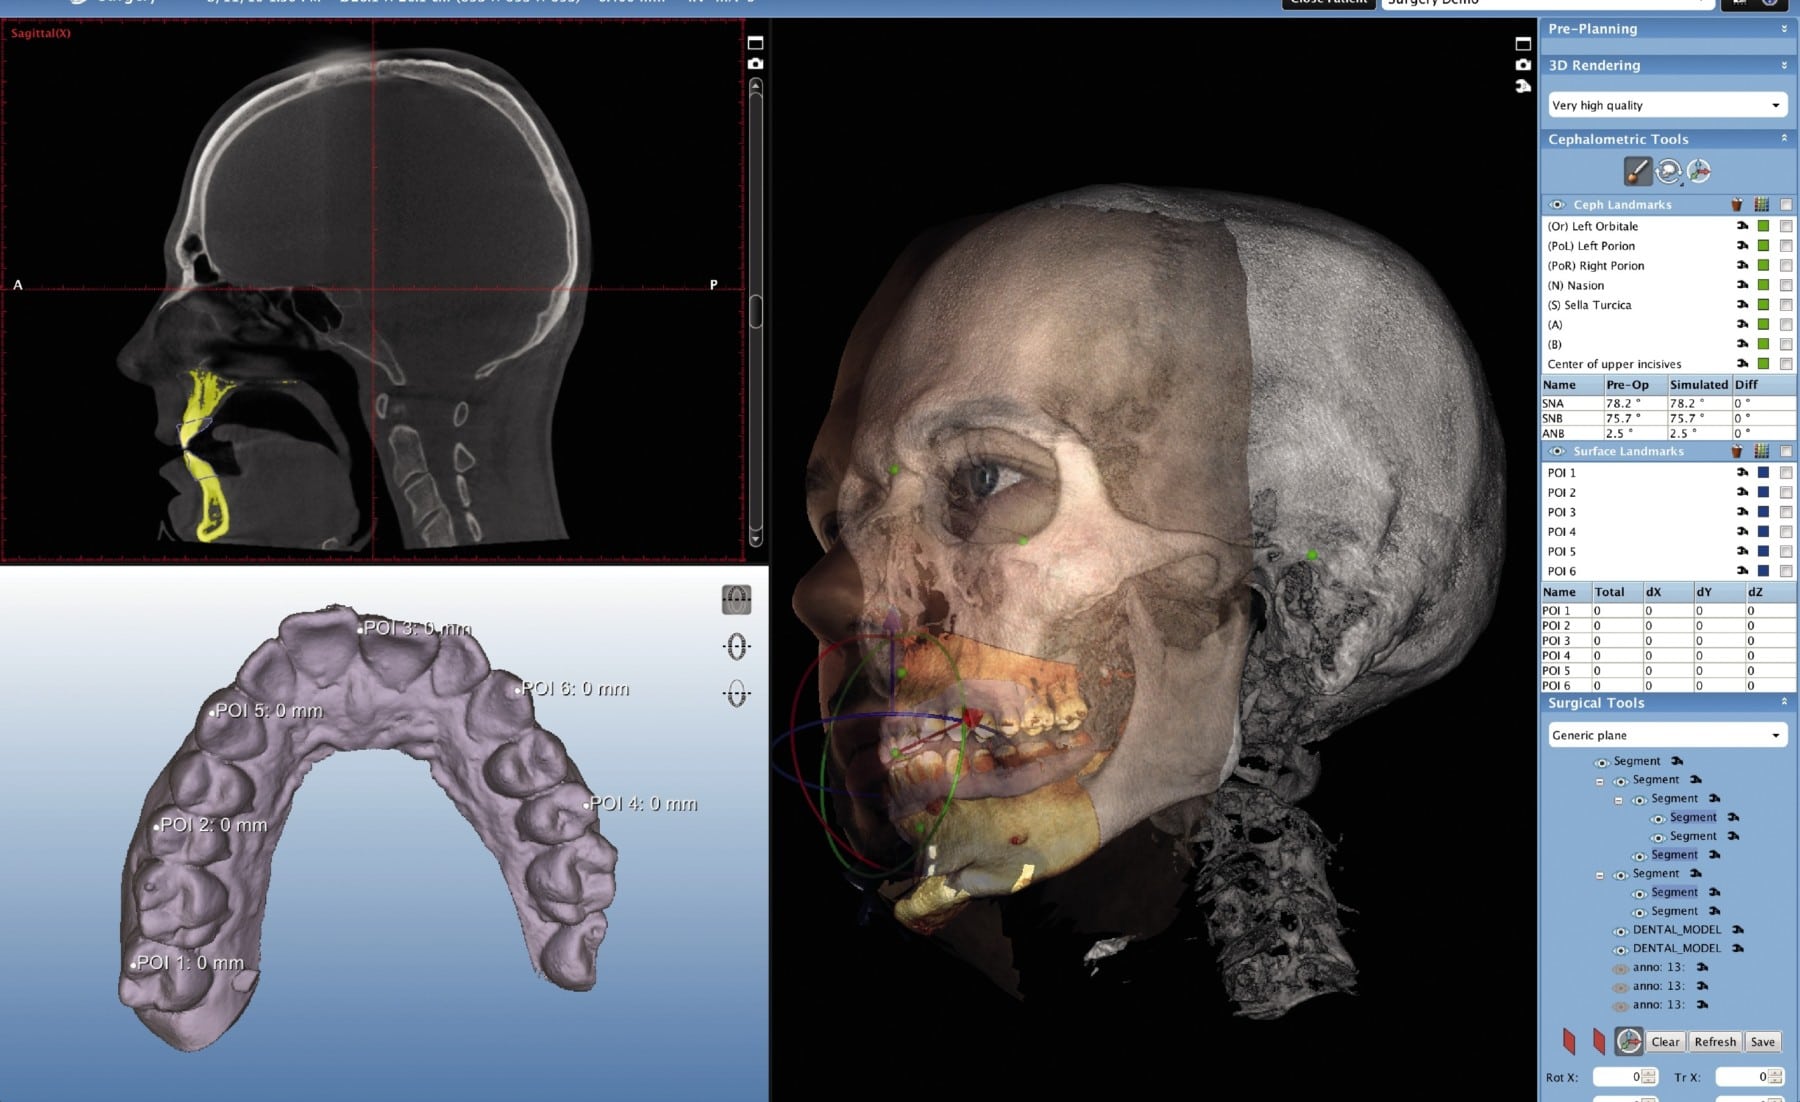

| Ortho/Ortho-Surg | TMJ analysis, airway volume quantification | Automated cephalometric tracing from CBCT (replaces 2D cephs) | AI-powered landmark detection (ISO/TS 23595:2025 compliant) |

Carejoy’s 2026 implementation exemplifies how API-first design transforms CBCT economics. Its RESTful API architecture (ISO/TS 22900-5:2026 compliant) enables:

- Zero-Touch Data Routing: Auto-transfers DICOM studies from CBCT to target CAD systems based on pre-defined rules (e.g., “all maxillary scans → 3Shape Implant Studio”)

- AI-Driven Workflow Triage: Prioritizes urgent cases based on CBCT findings (e.g., pathology flags), optimizing equipment utilization